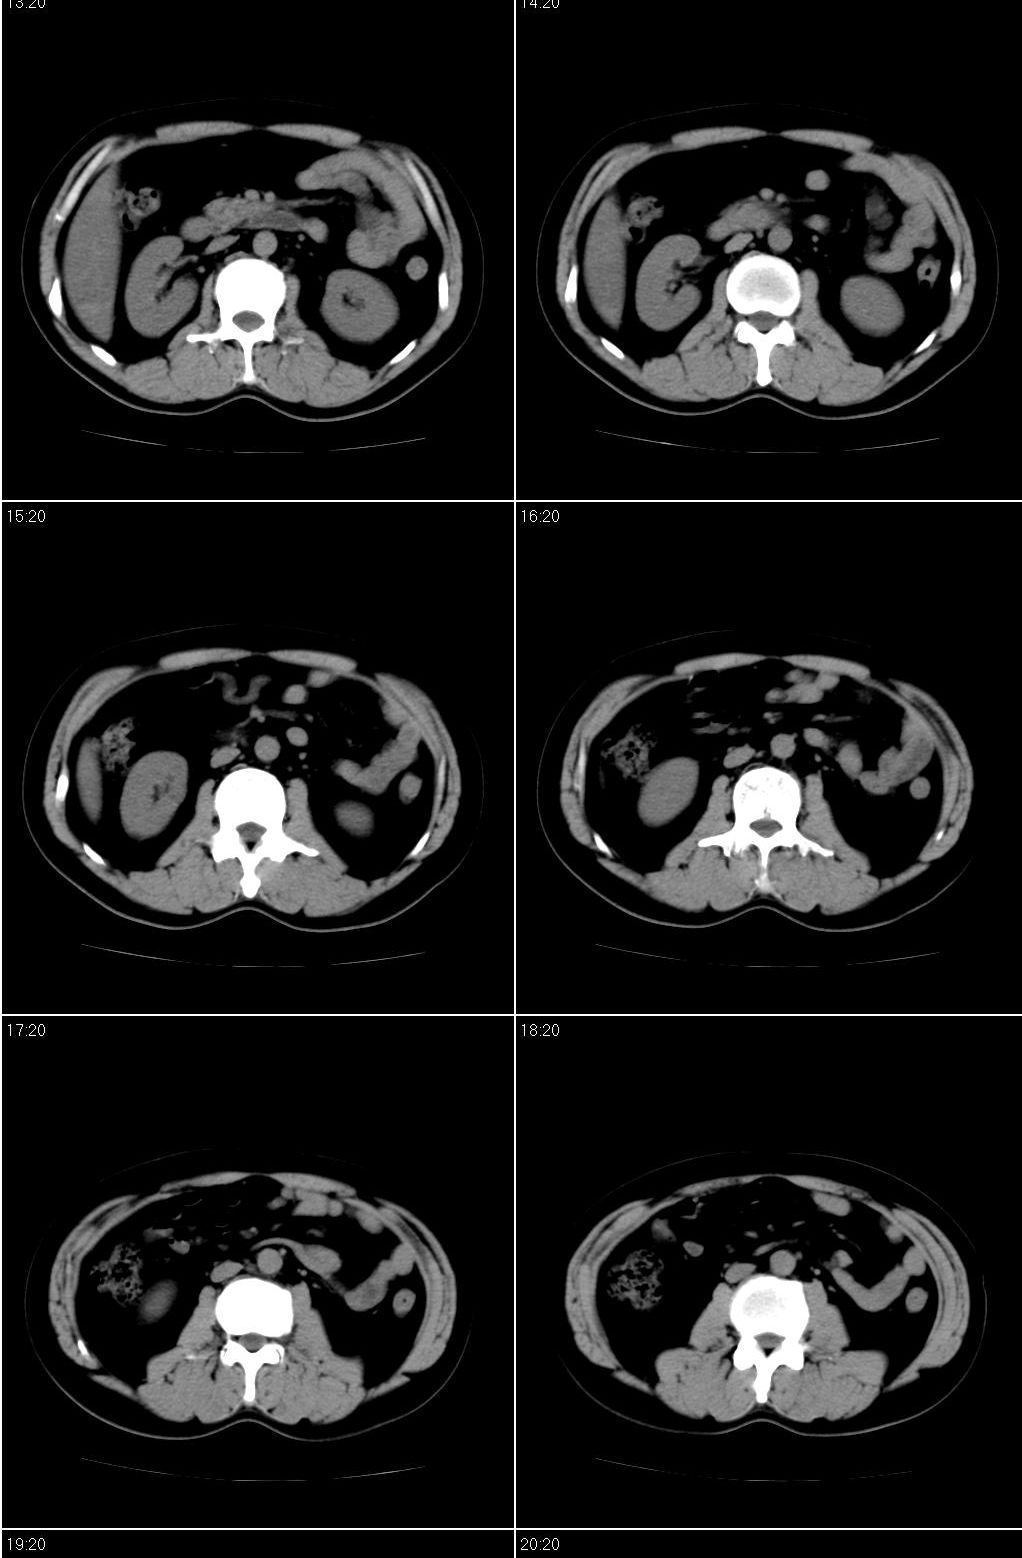

男,43岁。体检发现肝脏病变

结合增强扫描

我觉得肝左叶病变考虑fnh可能性最大。

增强后诊断很明确了,缓慢结节样强化:肝内多发血管瘤

从这个病例可以看出增强ct优势何其重要性和必要性。